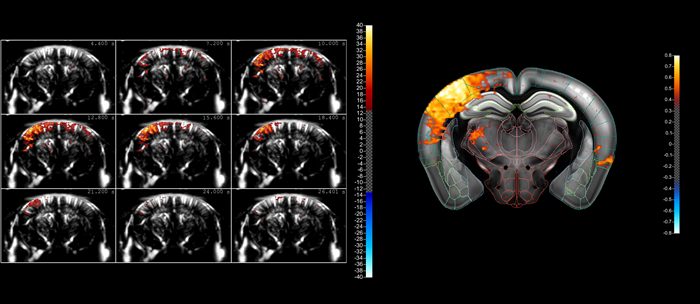

Indicative comparison of the imaging performance that can be achieved using cUS (left) and true fUS (right) for the rat brain (here involving a craniotomy), in both cases carried out by adjusting the scan settings on Iconeus One. fUS clearly has an advantage over cUS in terms of resolution and sensitivity. Image Credit: Iconeus

A typical compiled sequence of images acquired using fUS, showing the ‘lighting up’ of a part of the mouse brain as a result of whisker stimulation. The fact that blood flows in the brain can be in different directions within a small volume means that it’s better to image this activity using blood volume (using Power Doppler) rather than blood velocity (using color Doppler). However, our fUS– and microbubble-enabled ultrasound localization microscopy (ULM) technique – allows the actual blood velocities to be determined at high resolution should that information be needed

A typical compiled sequence of images acquired using fUS, showing the ‘lighting up’ of a part of the mouse brain as a result of whisker stimulation. The fact that blood flows in the brain can be in different directions within a small volume means that it’s better to image this activity using blood volume (using Power Doppler) rather than blood velocity (using color Doppler). However, our fUS– and microbubble-enabled ultrasound localization microscopy (ULM) technique – allows the actual blood velocities to be determined at high resolution, should that information be needed. Image Credit: Iconeus